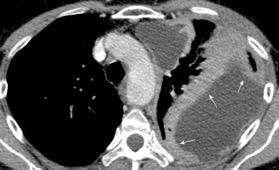

Marzo 2014: Perforación longitudinal distal secundaria a episodio de vómito (síndrome de Boerhaave). Derrame pleural izdo. que evoluciona a empiema.

Wang C-T et al. Tension hydropneumothorax in a Boerhaave syndrome patient: A case report . World J Emerg Med, 2021. Katabathina V et al. Nonvascular, nontraumatic mediastinal emergencies in adults:a comprehensive review of imaging findings. Radiographics. 2011.